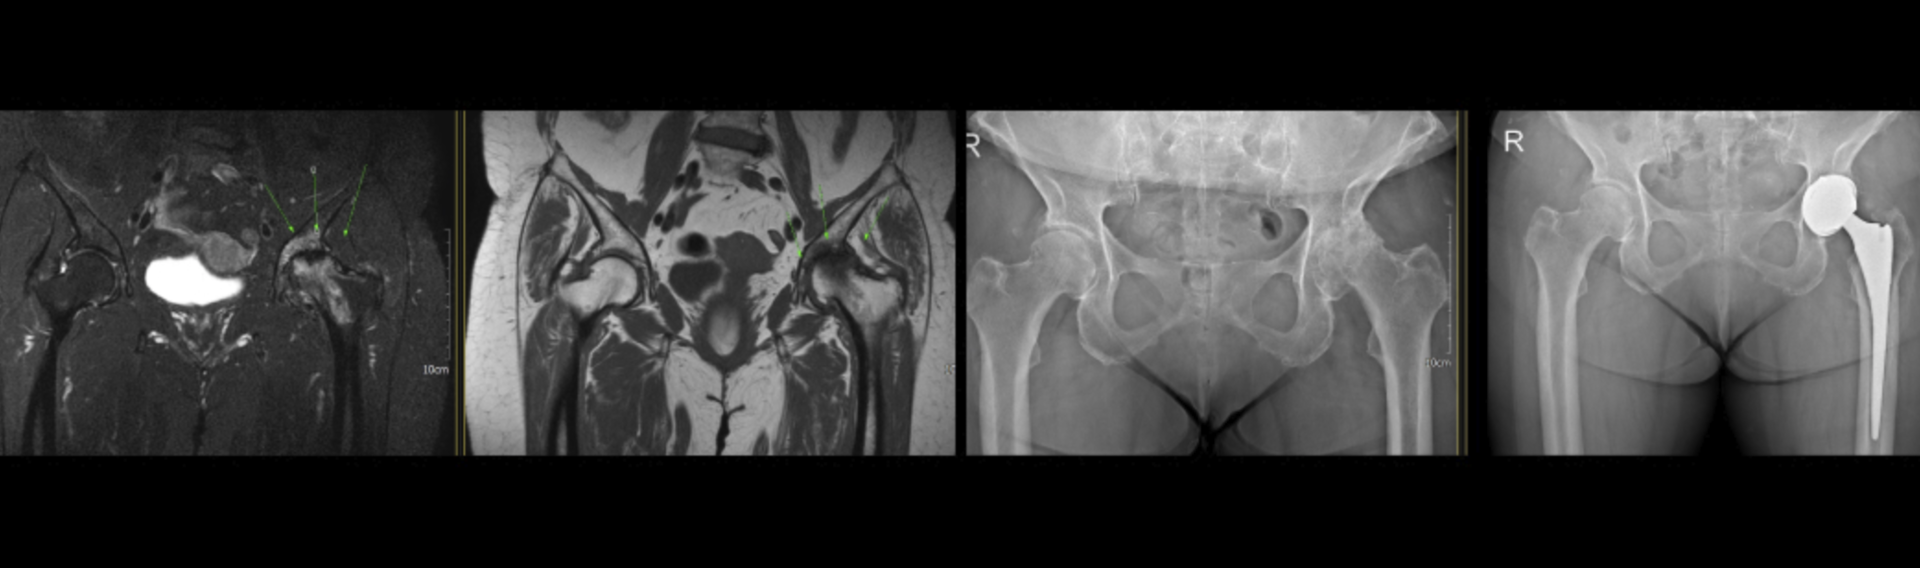

1. 인공관절 치환술

손상된 대퇴골의 골두를 제거하고 제거한 부분을 인공 고관절로 대체합니다.

2. 인공관절 반치환술

대퇴골두 관절 연골에 손상은 있지만 비구측의 문제는 없는 경우에 시행하며 대퇴골두만 제거하고 인공관절로 대체합니다.